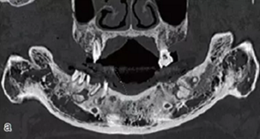

術(shù)前拍攝錐形束CT,進行三維重建和種植方案規(guī)劃。從CT圖像中可以看出頜骨內(nèi)有骨島和殘根,為避免種植體植入骨島區(qū),考慮在兩側(cè)頦孔區(qū)種植4~5顆種植體,采用套筒冠進行即刻修復(fù)。從重建的結(jié)果中可知前牙區(qū)牙槽嵴呈刀刃狀。種植方案為:對前牙區(qū)牙槽嵴進行截骨修整,并在兩頦孔之間的區(qū)域內(nèi)植入5顆種植體。

圖15 種植方案的規(guī)劃:a.患者的CT圖像的截面圖,圈紅處為骨島;b.患者摘掉活動義齒后的下頜;c.患者上下頜骨的CT三維重建;d.下頜骨截骨后模擬植入5顆種植體